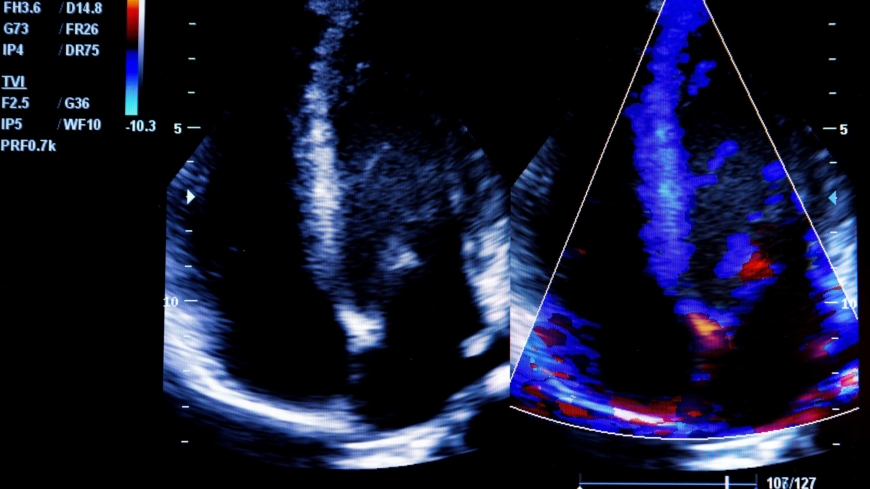

Enkammarhjärta brukar ofta upptäckas vid ultraljudsundersökningar. Foto: Shutterstock

En nedsatt förmåga att pumpa ut blod kan orsaka hjärtsvikt. Den låga syrehalten i blodet kan visa sig genom cyanos (blå hud, blåa läppar och blå slemhinnor). Enkammarhjärta och andra medfödda hjärtfel hos barn brukar ofta upptäckas vid ultraljudsundersökningar, antingen under graviditeten eller under barnets första levnadsvecka.